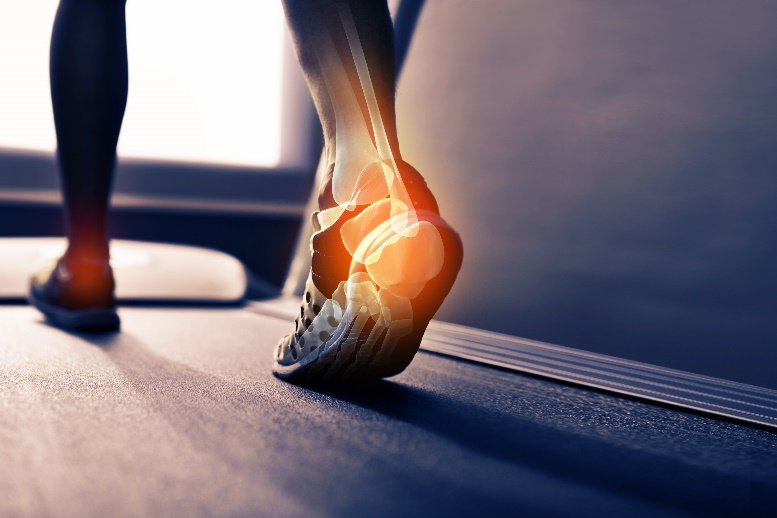

人體的骨骼會隨著我們的發育而變得愈來愈強韌,通常二十五歲時骨質強度會達到最高峰。若破骨細胞的活動力大於造骨細胞,則此不平衡的現象會造成骨量變少,長期累積會造成明顯骨質流失造成骨鬆。

(圖片來源:Getty)